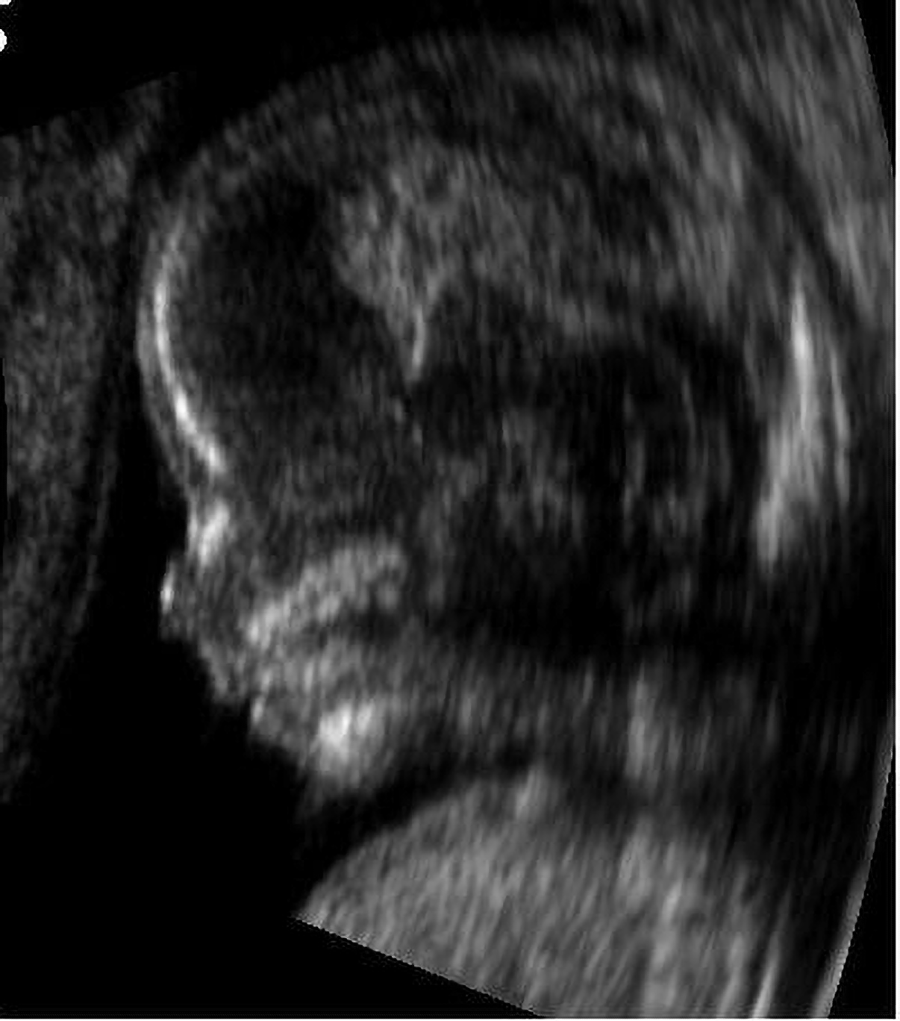

3d. Ultrasounds

Echogenicity, meaning the way that structures respond to sound to produce an image, varies in ultrasounds. Hyperechoic (more echogenicity) means bright or white and represents structures such as bone, fat, and calcifications. Hypoechoic (less echogenicity) means darker than the surrounding tissues and represents structures such as tumors and cysts. Anechoic means completely black and represents structures such as fluid-filled cysts and blood vessels.

Acoustic shadowing occurs when there is a dark area behind a dense structure that is blocking sound waves.

The ultrasound below shows the head of a 14-week-old fetus.

An ultrasound shows 14-week-old fetus.